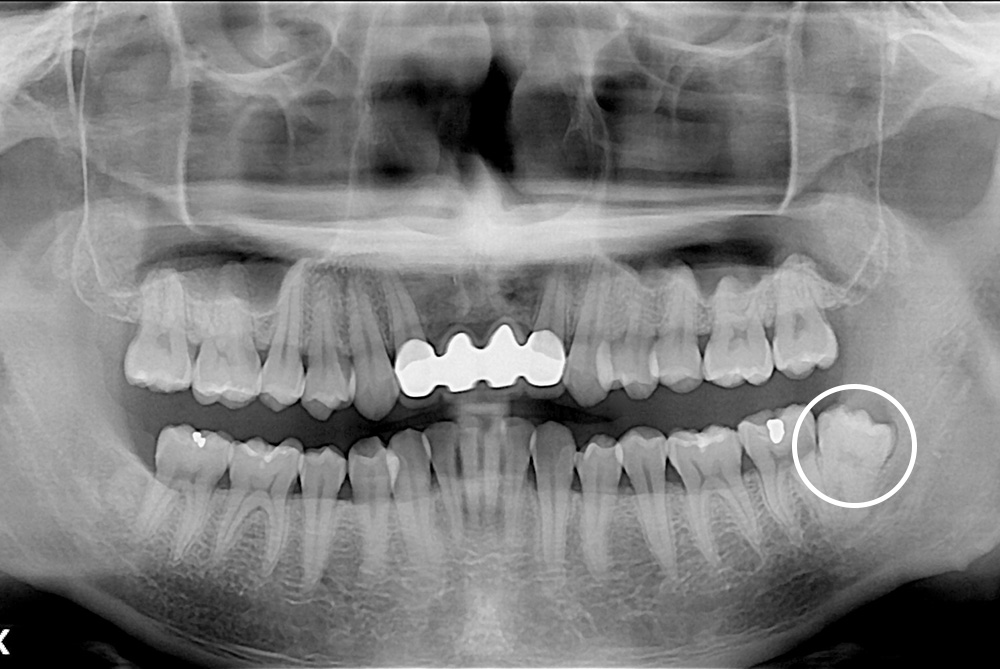

[사랑니] 매복 사랑니 발치

치료전 : 2017-10-18

치료후 : 2017-10-28

세종치과는 구강악안면외과학 박사이신 원장님이 발치하는 치과입니다.